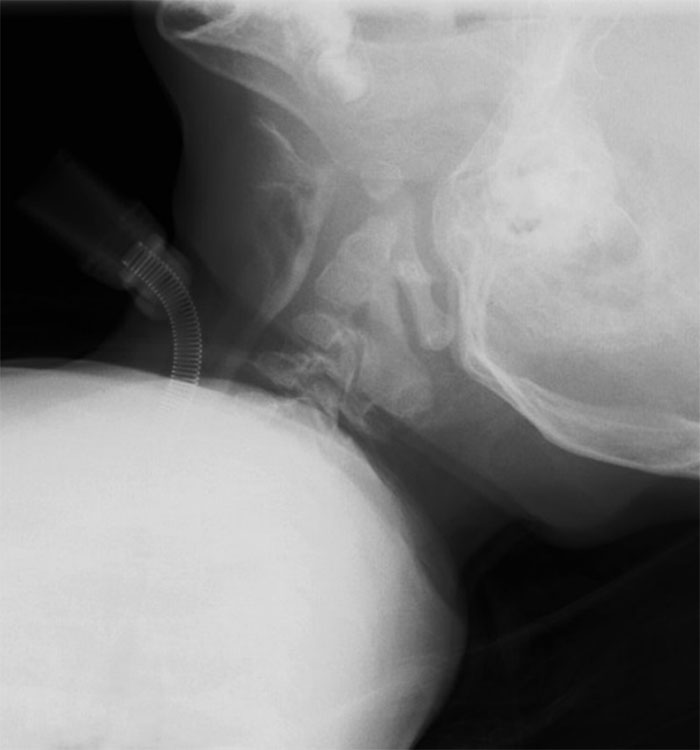

透視検査

透視検査は、エックス線を利用して体内の様子を透視しながら行う検査です。

胃チューブの交換や嚥下検査などで用いられ、造影剤を用いることでより消化管や飲み込む様子などがわかりやすくなります。